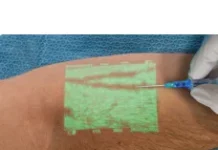

Всі перераховані вище ознаки є для трихомоніазу основними, але вони можуть сигналізувати і про наявність інших інфекцій або захворювань, що передаються статевим шляхом. Іноді симптоматика захворювання дуже слабка, невеликий дискомфорт в області живота, слабкі виділення, на які жінка навіть не звертає уваги, відсуває думки про відвідини гінеколога на другий план, посилюючи ситуацію. Підтвердити наявність захворювання зможе тільки фахівець за допомогою лабораторного аналізу (взяття мазка) і діагностики.

Схема лікування трихомоніазу у жінок призначається лікарем індивідуально, у відповідності зі стадією розвитку захворювання. Варто враховувати фізіологічні особливості організму жінки і типу розповсюдження інфекції. Як лікувати трихомоніаз у жінок? Основні правила:

- Зовнішньо, як допоміжні засоби, застосовують ліки у вигляді гелів, свічок, кремів.